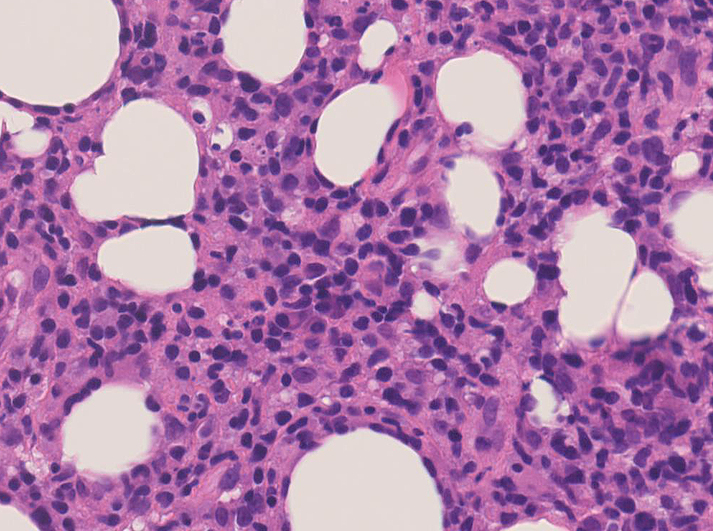

リンパ腫の定義: SPTCLは成熟細胞障害性T細胞(cytotoxic T-cell)由来で、皮下組織に脂肪識炎に似た組織像を呈しながら増殖する悪性リンパ腫。

皮下組織に優位な, 小~中型 Tリンパ球の密な浸潤が特徴。ときに大型リンパ球や組織球が混在する。 リンパ球の異型は, わずかなものから明瞭な異型を示す症例までさまざまである。